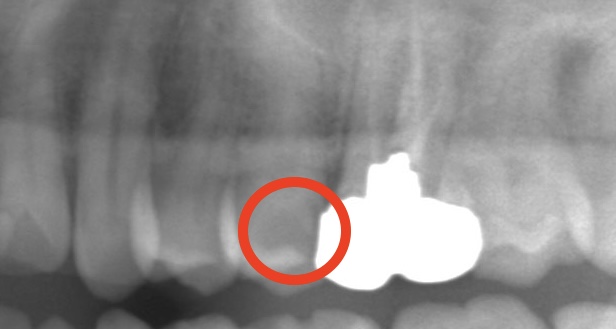

白いところは奥歯に金属がはまっている部分です。

その隣の歯に、”黒い影”があることに気づきますか?

ここです。

はっきりむし歯があることがわかります。

しかもけっこう大きなむし歯です。

レントゲン検査をしていれば一目瞭然でわかる大きさのむし歯です。